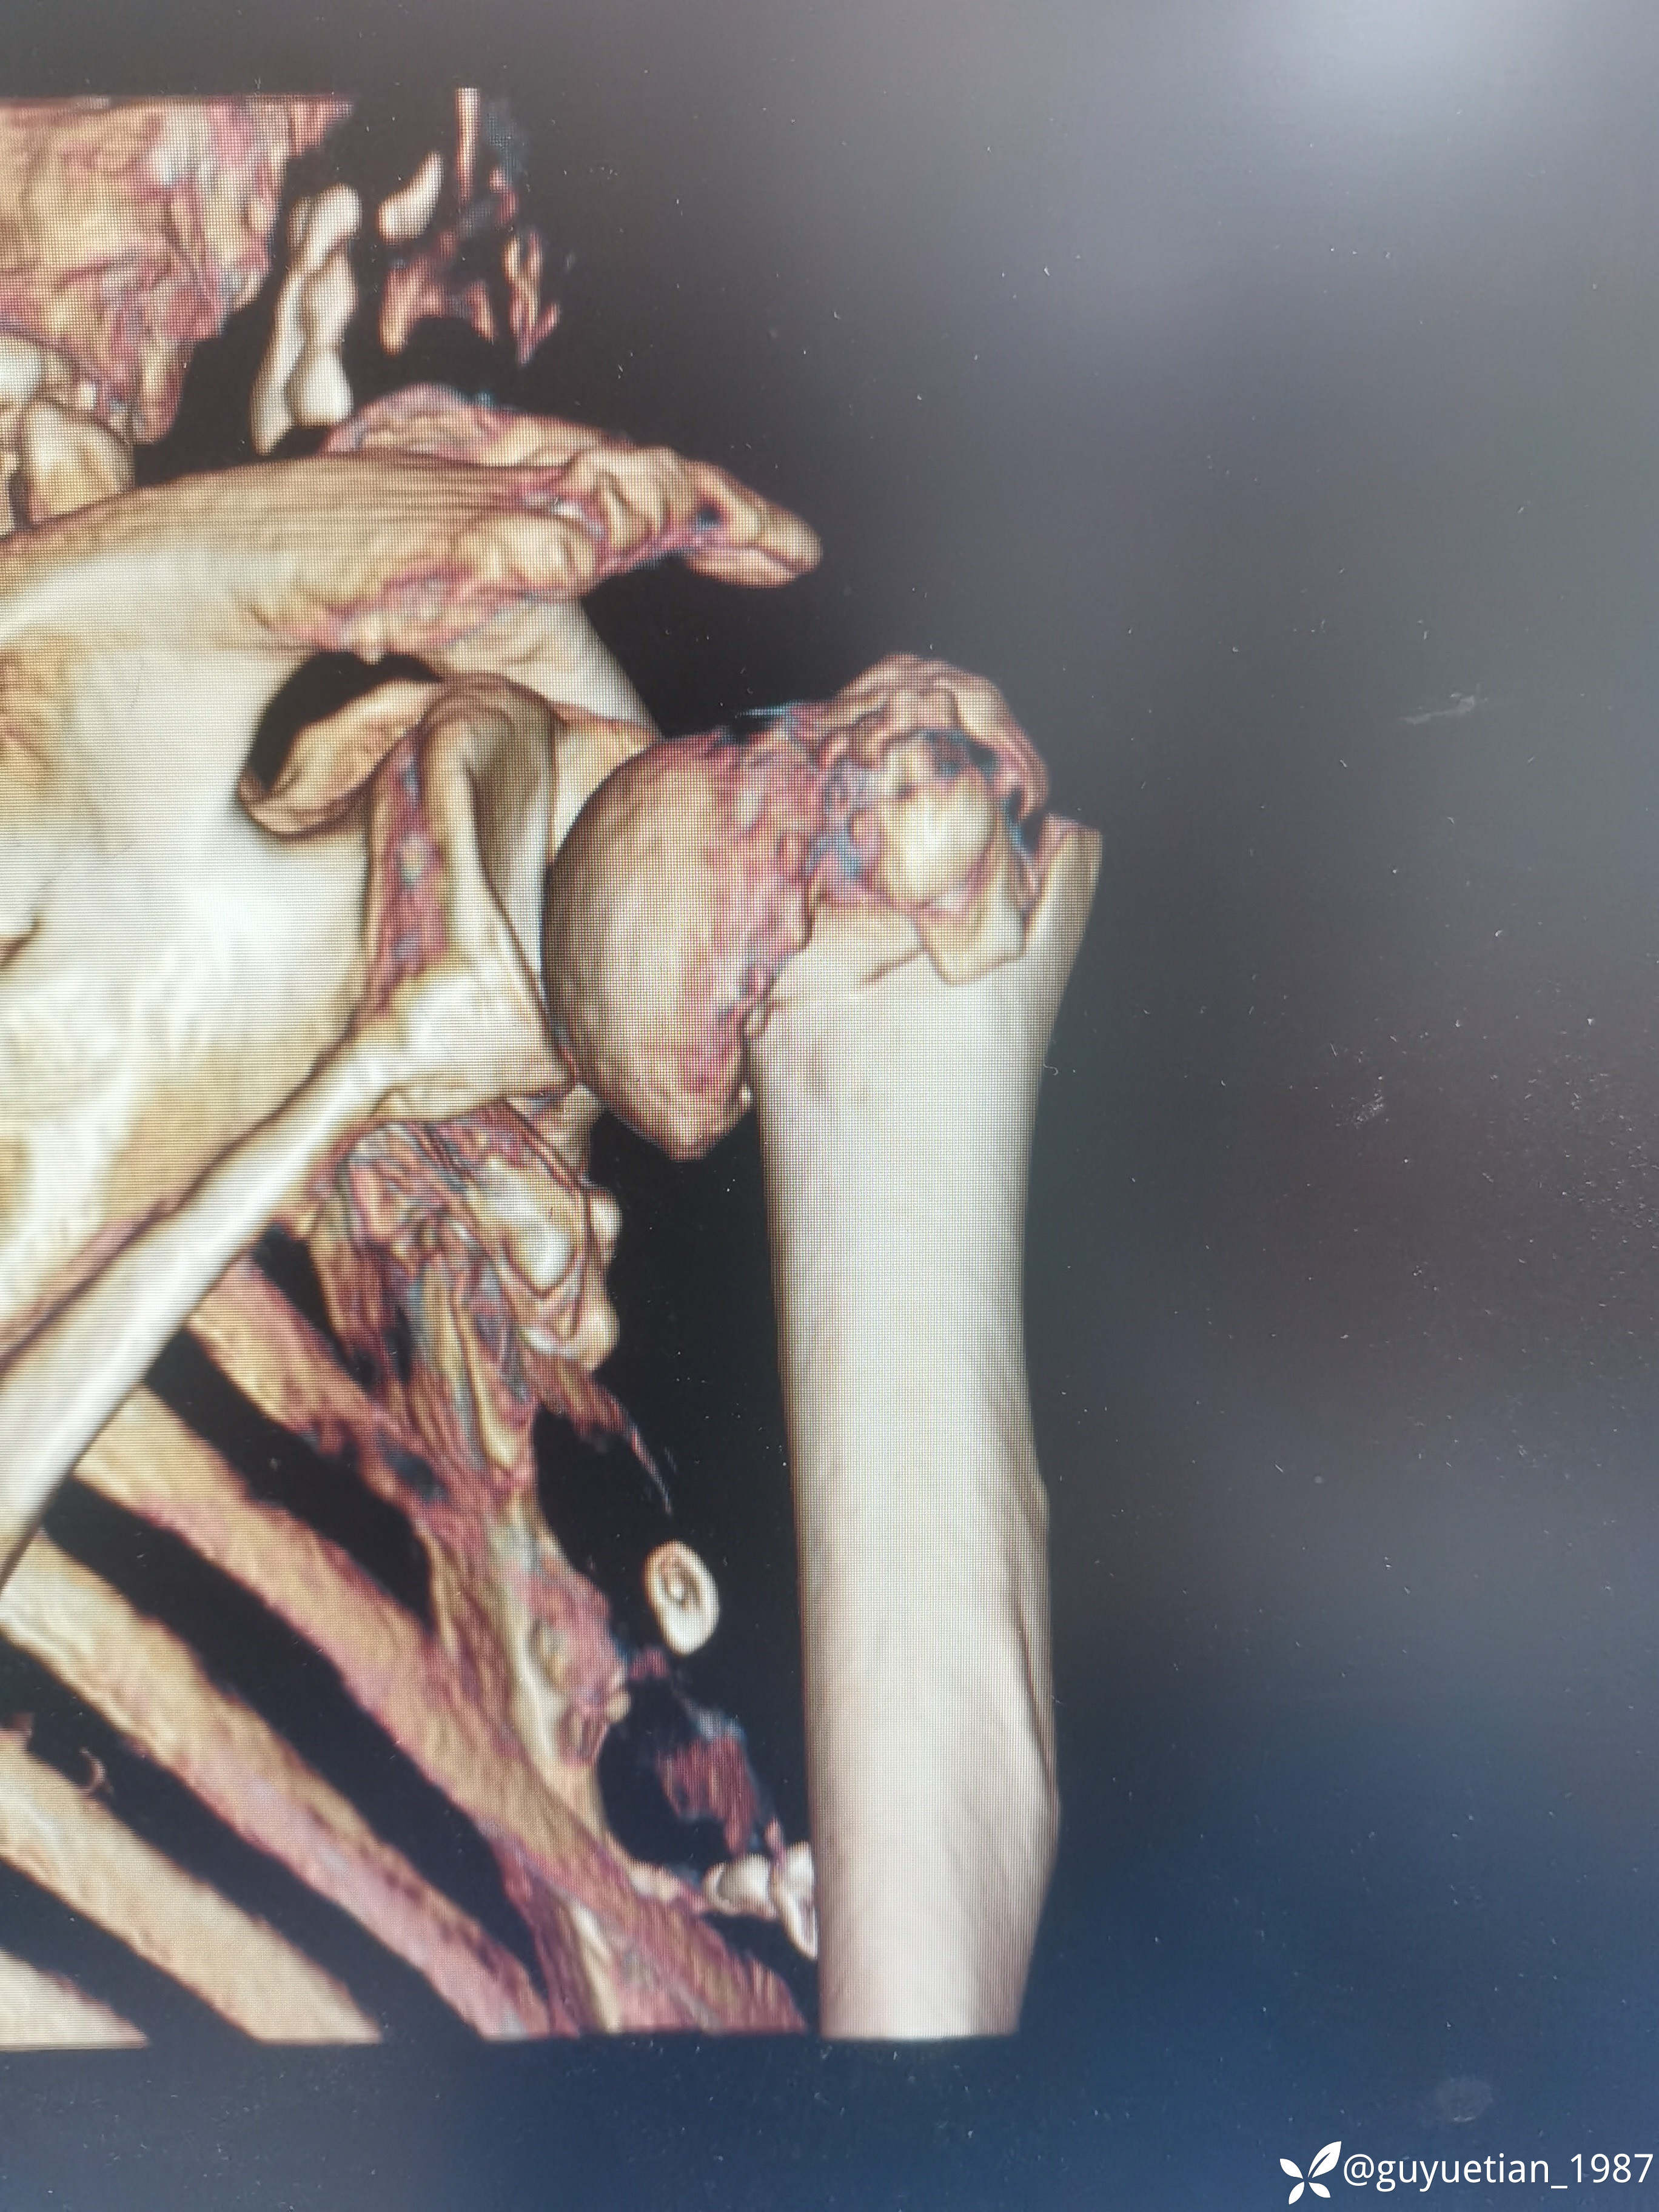

内收型,向前成角

家属沟通后倾向于保守,那就尽力而为

可以接受,夹板固定,嘱耸肩、握拳锻炼。

手术做也没有问题,关键在于年龄,这个年龄这个骨量后期功能不见得多好。充分沟通前提下的保守不见得比手术差。